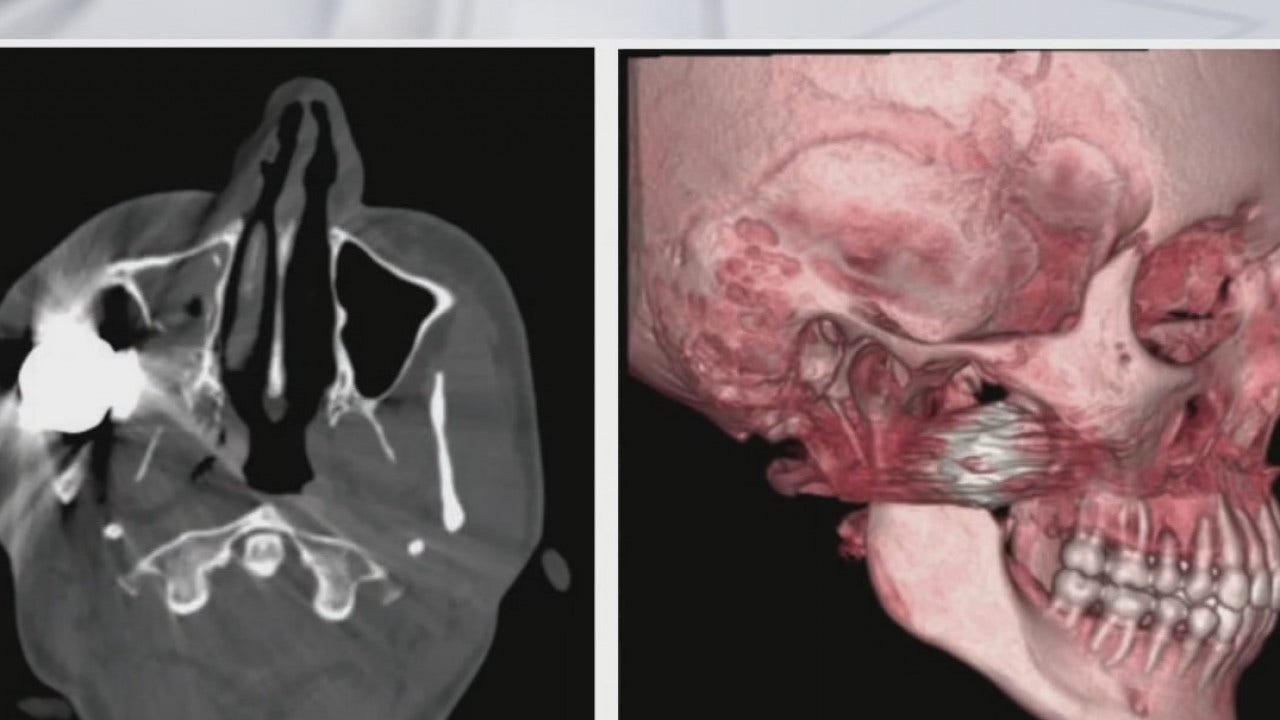

“Some of them are penetrating injuries, some of them to the head, some of them to the soft tissues of the chest, some of them to the arms and legs, a number of different lacerations and bruises,” said Dr. Kris Olson, Surgical Resident at the University Of Texas at Austin Dell Medical School.

“Those injuries were severe, and penetrating injuries that we didn't anticipate seeing,” said Dr. Olson.

Out of those 19 patients, there were multiple head injuries and facial fractures. Some patients retained bean bags in their wounds.